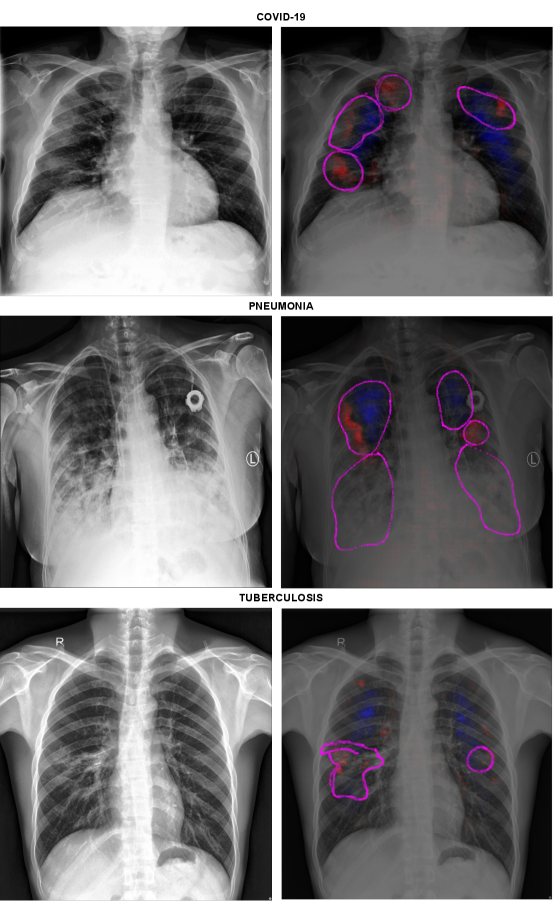

Figure 2 shows heatmaps for the COVID-19 and TB detection applications (without synthetic bias). The tasks use mixed training datasets, which are known to cause background bias and shortcut learning[36],[13],[15],[14]. Accordingly, the LRP heatmaps for a standard classifier (DenseNet121) demonstrate a significant influence of background features over the classifier’s decisions, indicating shortcut learning. Supporting this finding, Tables 2 and 5 show that the model’s generalization performance was impaired. It achieved only 0.546 +/-0.01 and 0.566 +/-0.05 average F1-Scores in the COVID-19 and TB o.o.d. test datasets, respectively. Conversely, the heatmaps in Figure 2 indicate that the ISNet is the DNN with the least amount of background attention in the two tasks. Quantitatively supporting the information in the heatmaps, the ISNet’s o.o.d. generalization performance surpassed all other models in TB and COVID-19 detection (Tables 2 and 5), indicating that it could better minimize the influence of background bias over the classification decisions.

Figure 2: Heatmaps (Layer-wise Relevance Propagation/LRP for convolutional networks and attention rollout for Vision Transformer) for positive COVID-19, Pneumonia and tuberculosis. The Image’s true class is stated above the figures, the DNN that produced the heatmap is identified on the left. For LRP, red colors indicate areas that the DNN associated to the true class, blue colors are areas that decreased the network confidence for the class. For attention rollout, red indicates the DNN attention. White represents areas with little influence over the classifiers. Attention outside of the lungs (foreground) is undesirable